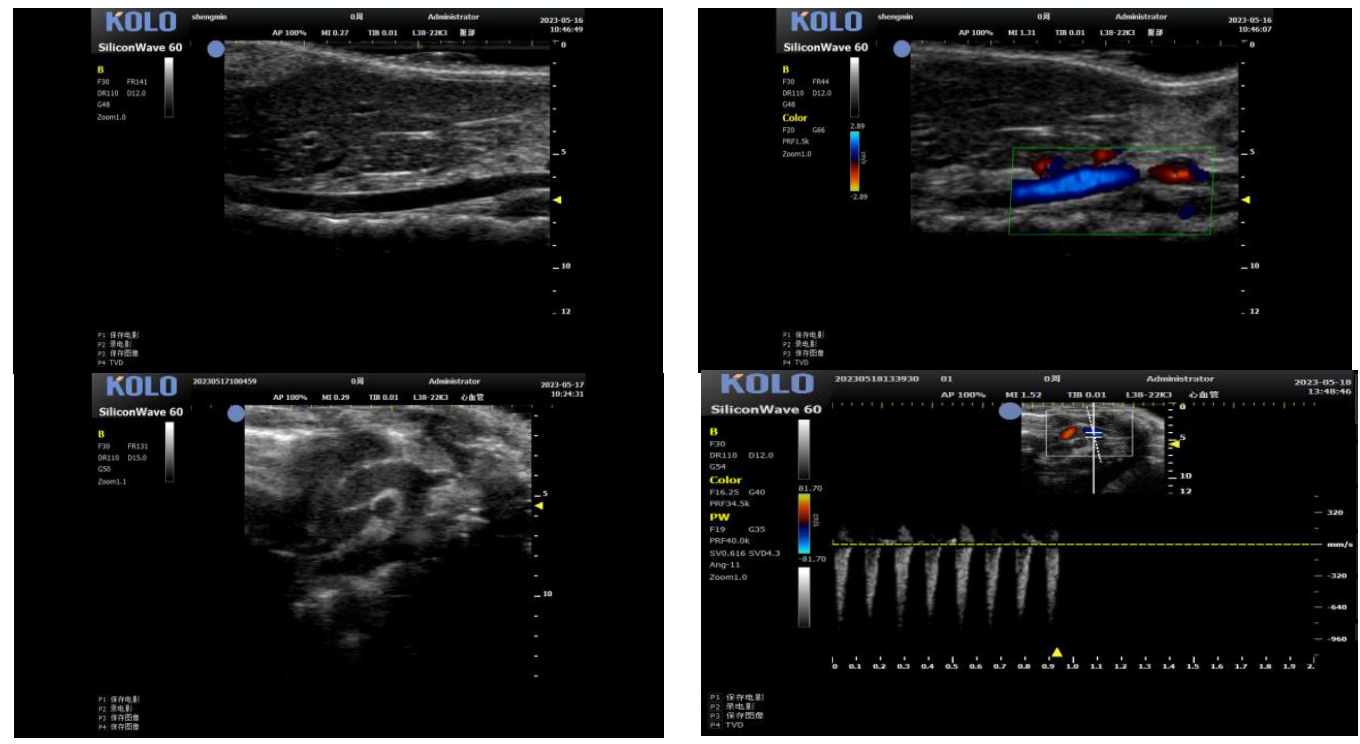

3.1 腹主动脉(长+短轴+管壁距离测量+血流流速)

3.2 颈动脉(长轴)